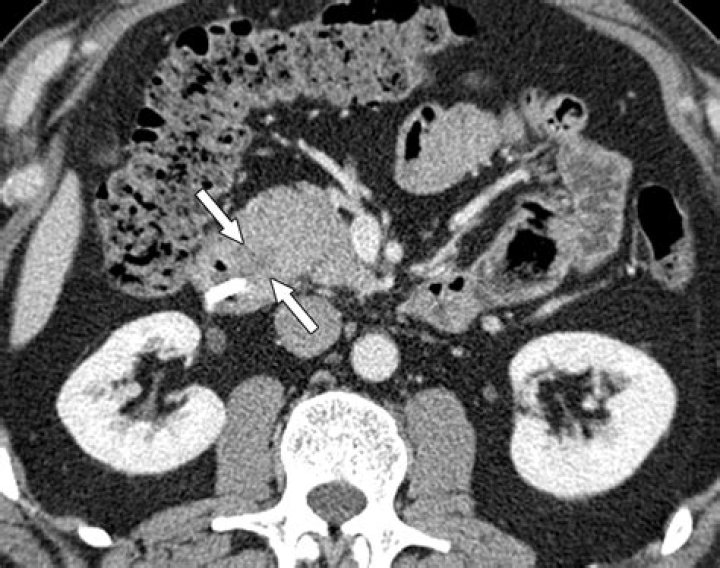

A relatively specific main pancreatic duct change of AIP is multifocal narrowing, and this may be depicted on CT or MRCP (1, 19).

CT features of chronic pancreatitis that can be visualized on CT scans include dilatation of the main pancreatic duct; calcifications; changes in size, shape, and contour; pseudocysts; and bile duct changes. (See the CT images of chronic pancreatitis below.)